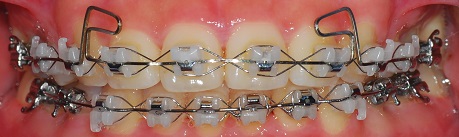

이래서 이번달에 무시무시한 다리같은걸 위 와이어에 장착했습니다

그 철사는 윗 니들을 들어올리는 역할을 한다구 해요

그리고 그 철사에 고무줄을 걸기로 했습니다. 이번엔 잘 걸어야 겠어요ㅎㅎㅎㅎ

정면사진

측면 사진

예전에는 윗니와 아랫니를 다물었을 때 공간이 있었는데 지금은 아예 없어졌어요~